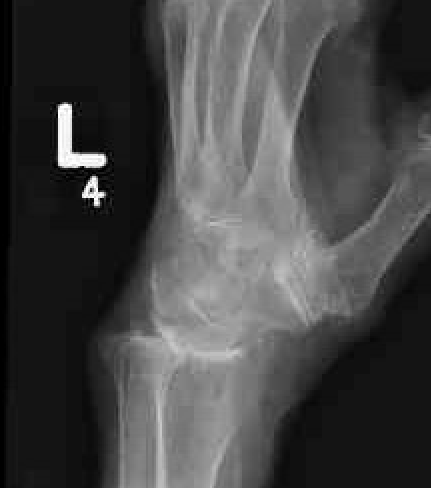

SNAC wrist